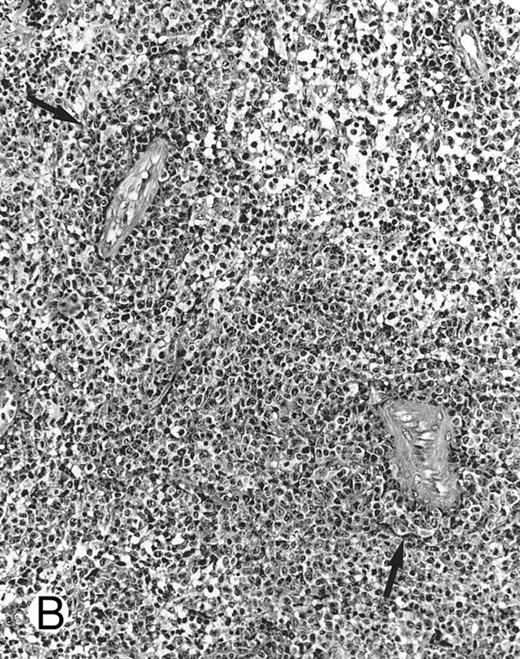

Nasal-type NK/T-cell lymphoma presenting as nodular skin lesion (case no. 28). (A) The skin shows focal necrosis of the epidermis and ulceration (arrow). (B) The lymphoid infiltrate in the dermis shows angiocentricity, as evidenced of the higher density of cells in the expanded walls of the blood vessels (arrows).

Histologically, the lymphomatous infiltrate was diffuse or patchy, with angiocentric and angiodestructive growth being observed in 30 cases (88.2%) (Figs 1 and 2). The cytologic composition was variable from case to case, including predominance of small cells, medium-sized cells, or large cells, or a mixture of these cell types (Fig 2 and 3). The tumor cell nuclei frequently showed irregular foldings and granular chromatin (Fig 2B). The larger cells possessed distinct nucleoli. The cytoplasm was moderate in amount and often pale. Karyorrhexis was usually prominent. Zonal tumor cell death, focal or confluent, was evident in 27 cases. In the 14 cases for which Giemsa-stained touch preparations were available, azurophilic granules could be identified in at least some of the neoplastic cells.

There were very few to numerous granular lymphocytes in the peripheral blood. Some of the granular lymphocytes were indistinguishable from normal large granular lymphocytes, with round nuclei, dense chromatin, and pale cytoplasm with fine azurophilic granules (Fig 5A). Some granular lymphocytes had larger nuclei with more open chromatin and distinct nucleoli (Fig 5B); occasional nuclei could show indentations. The azurophilic granules were sometimes large and coarse. There were also circulating normoblasts and immature myeloid cells. Marrow involvement ranged from subtle to extensive. In histologic sections, irrespective of site, there was a monotonous infiltrate of medium-sized cells with round nuclei and fairly condensed chromatin (Fig 6). Karyorrhexis was prominent. The infiltrate was diffuse, interstitial, or angiocentric.